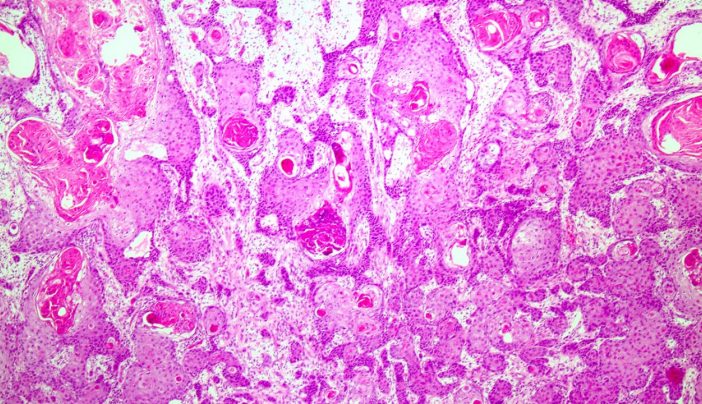

Squamous Cell Carcinoma Skin Cancer Symptoms Causes Treatment

_squamous_cell_carcinoma_histopathology.jpg/220px-Oral_cancer_(1)_squamous_cell_carcinoma_histopathology.jpg)